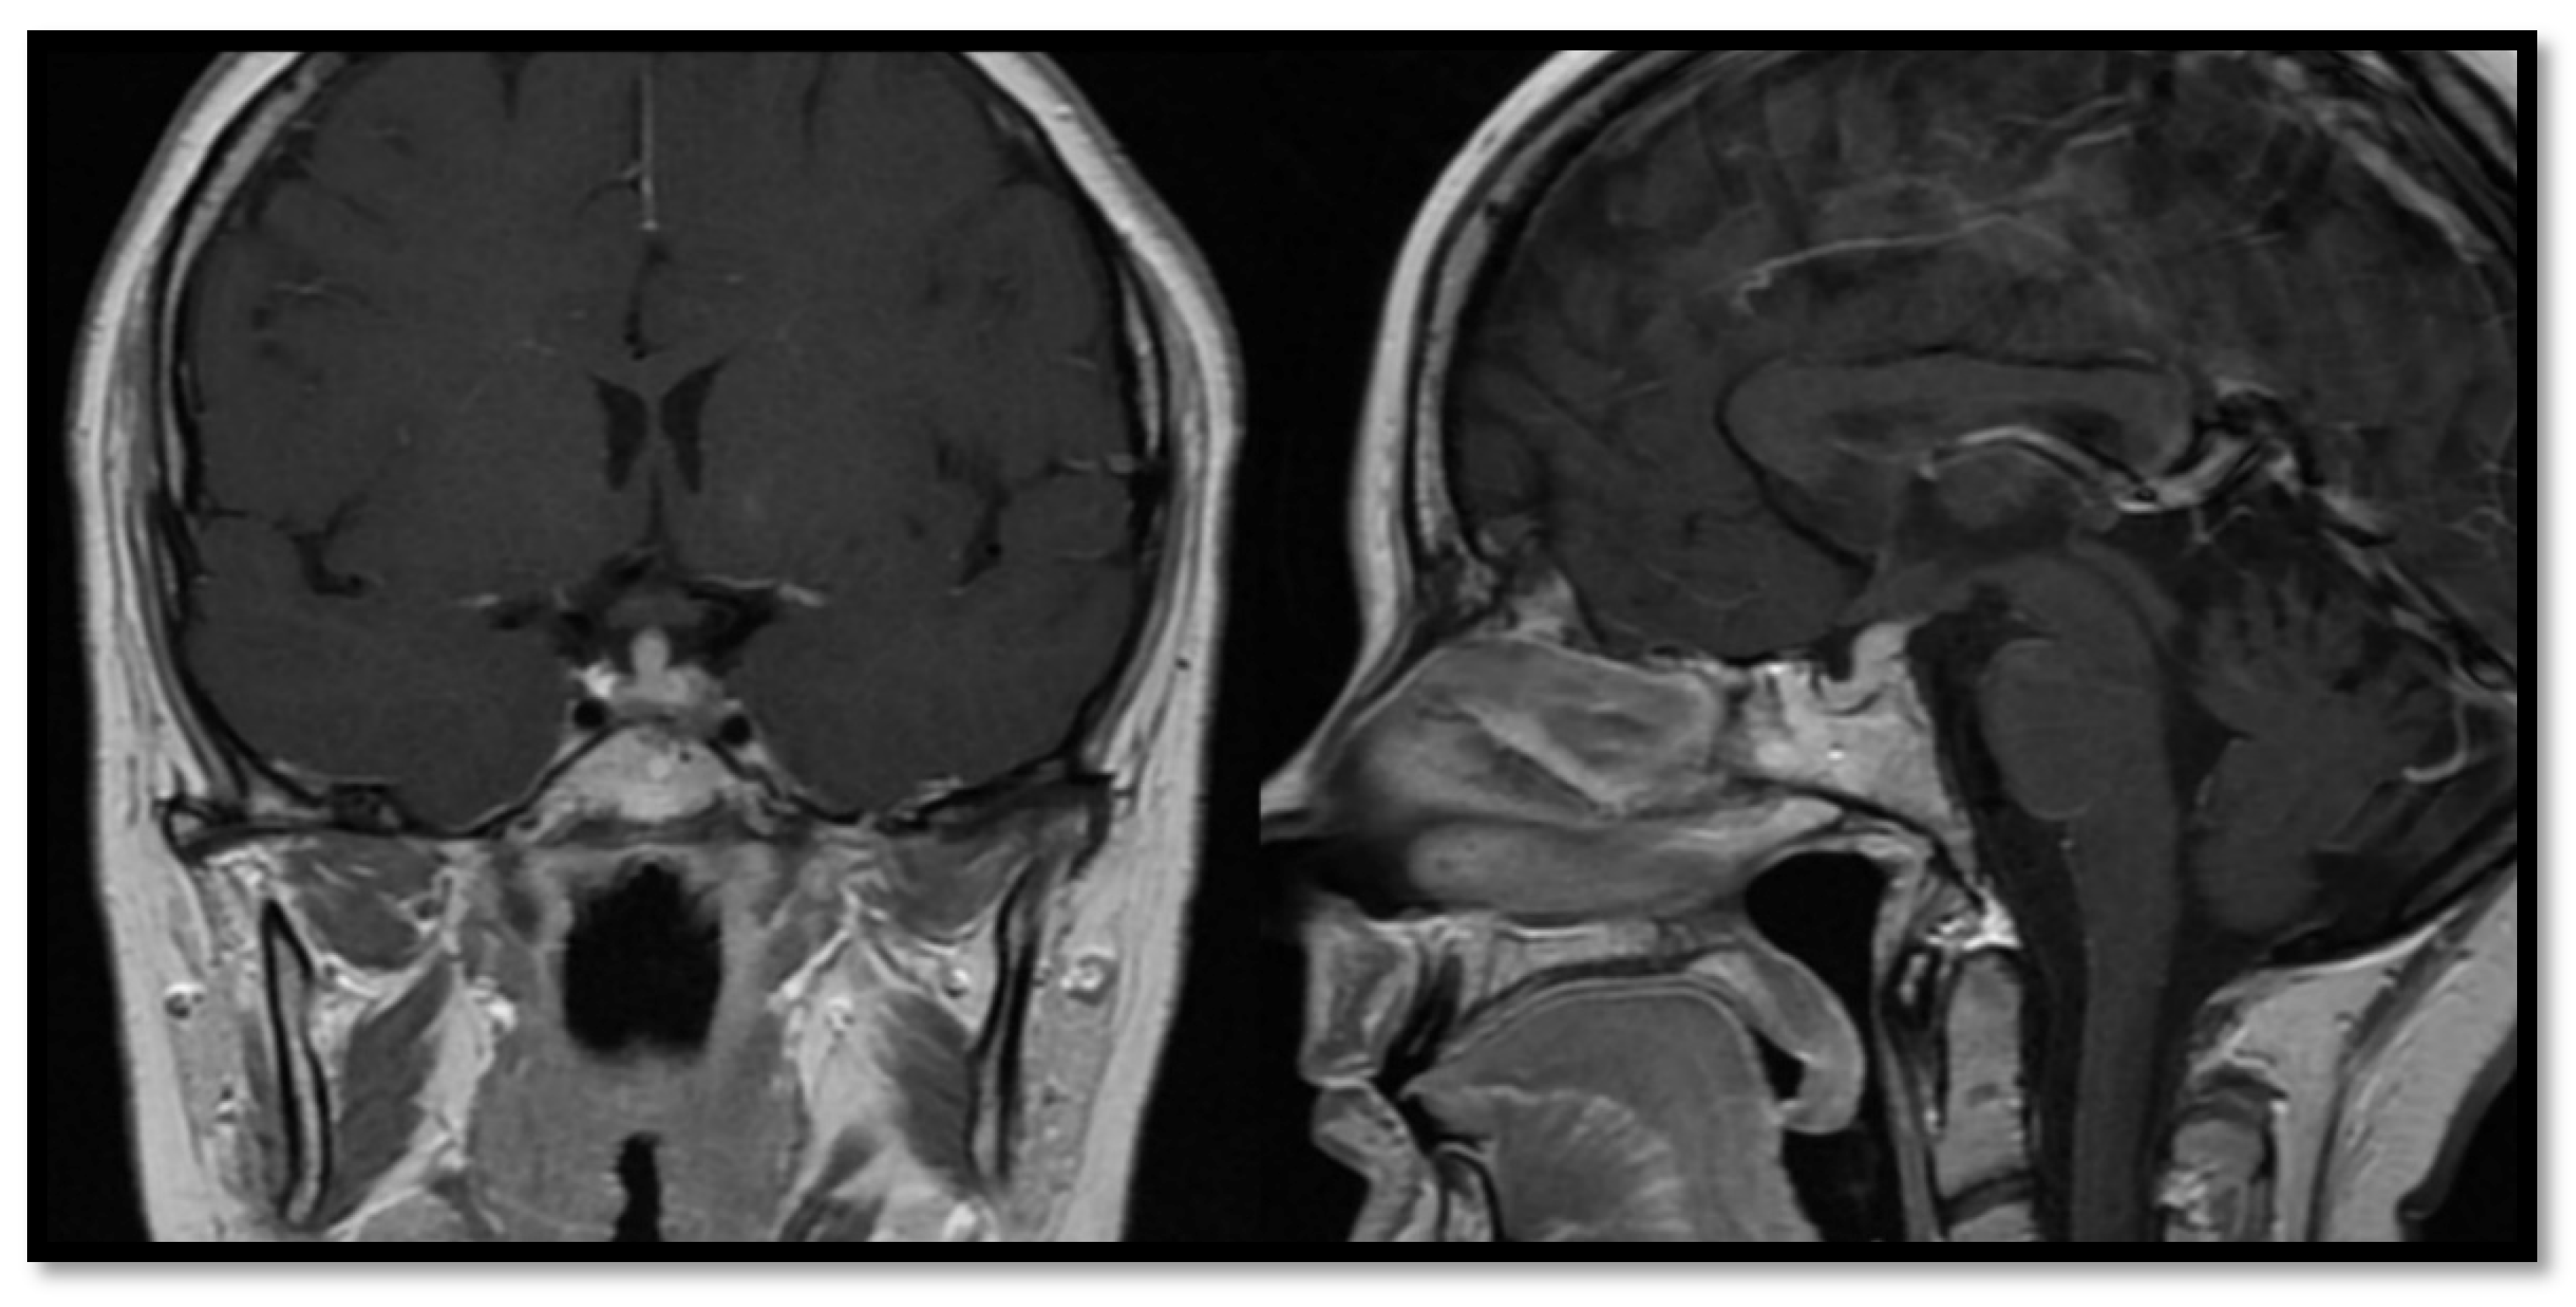

3.1. Congenital Abnormalities

3.4. Imaging